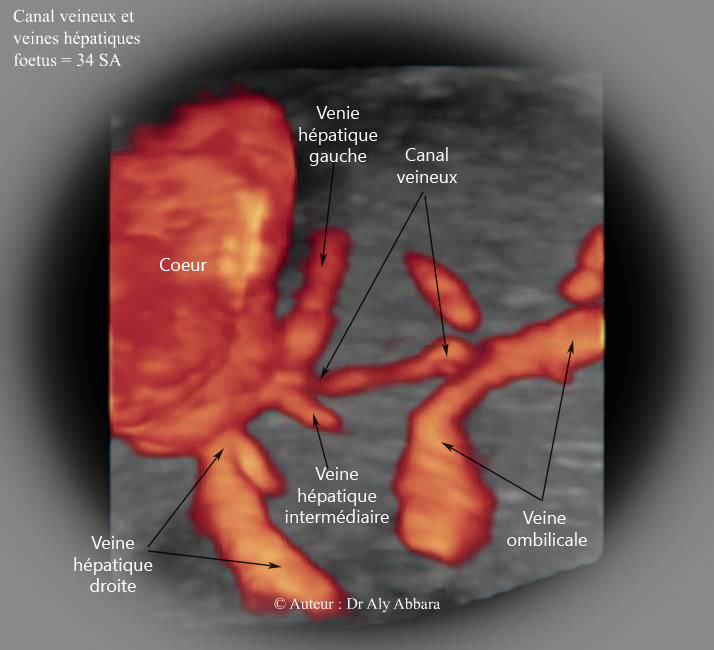

Les rapports anatomiques entre le canal veineux (ductus veineux) et les trois veines hépatiques

Images échographiques montrant les rapports anatomiques entre le canal veineux (branche de la veine ombilicale gauche) les veines hépatiques : on peut constater sur l'image que la terminaison du canal veineux à la partie terminale de la veine cave inférieure se situe directement au-dessous des terminaisons des veines hépatiques gauche et intermédiaire.

Fœtus âgé de 34 SA dans le cas présent.

Les veines hépatiques sont souvent au nombre de trois : la veine hépatique droite ; la veine hépatique intermédiaire et la veine hépatique gauche. Ces veines quittent le foie au niveau de sa face supérieure dorsale et plus précisément de l'area ndua (zone rugueuse dépourvue de péritoine, car sa surface est formée par seulement la capsule conjonctive du foie).

Anatomiquement, la terminaison des veines hépatiques se trouve sur la paroi antérieure de portion terminale de la veine cave inférieure dans une zone située juste sous le diaphragme ; chez l'adulte, cette terminaison n'est éloignée de l'oreillette droite du cœur que de quelques centimètres ; donc dans les insuffisances cardiaques droites, il peut se produire un reflux de sang de l'oreillette droite vers le foie, ce reflux est à l'origine de l'hépatomégalie congestive dans ces pathologies cardiaques.